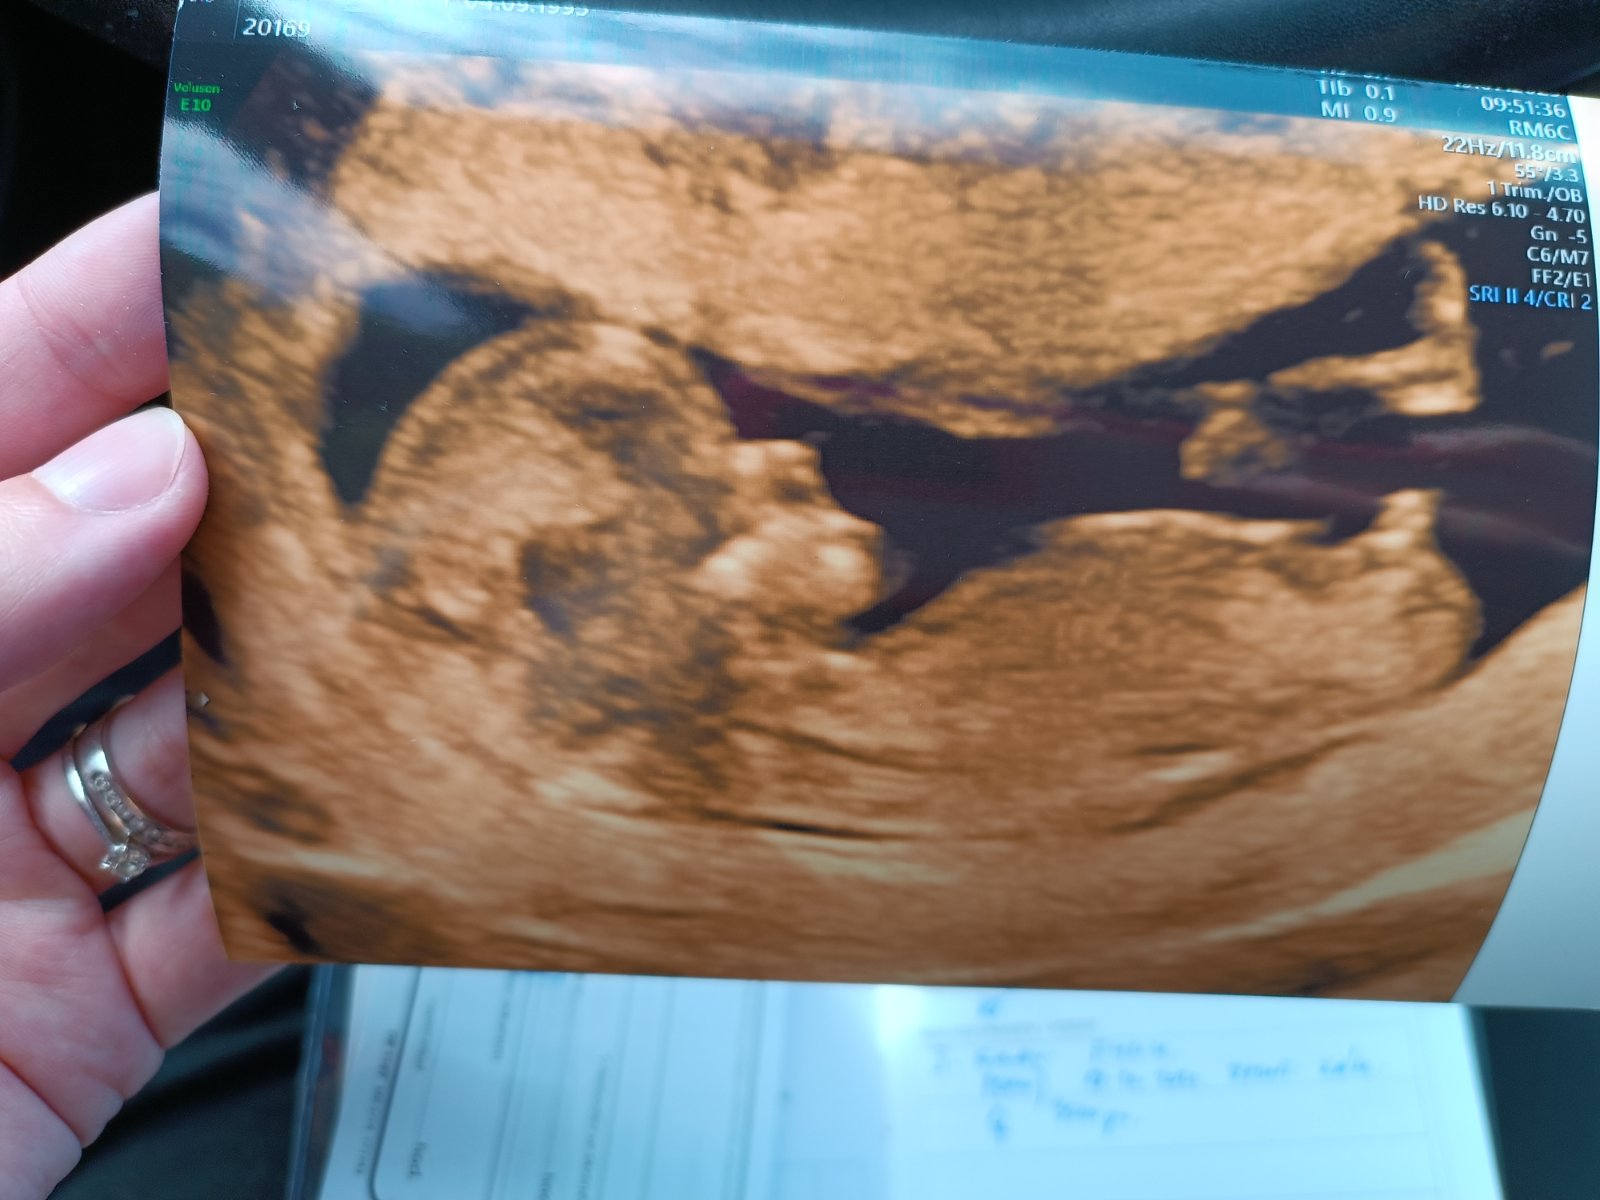

Určitě tě nemine 3D ultrazvuk.

@horhana esi je to hrbolek, tak kluk 100% 😁